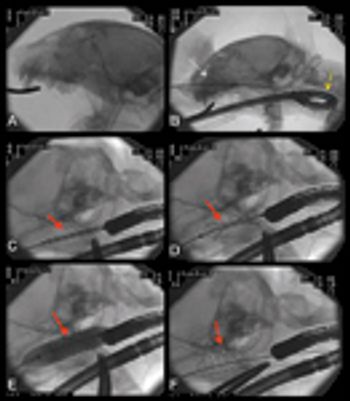

See how interventional radiography and endoscopy can help you identify and treat this abnormality in this case study.